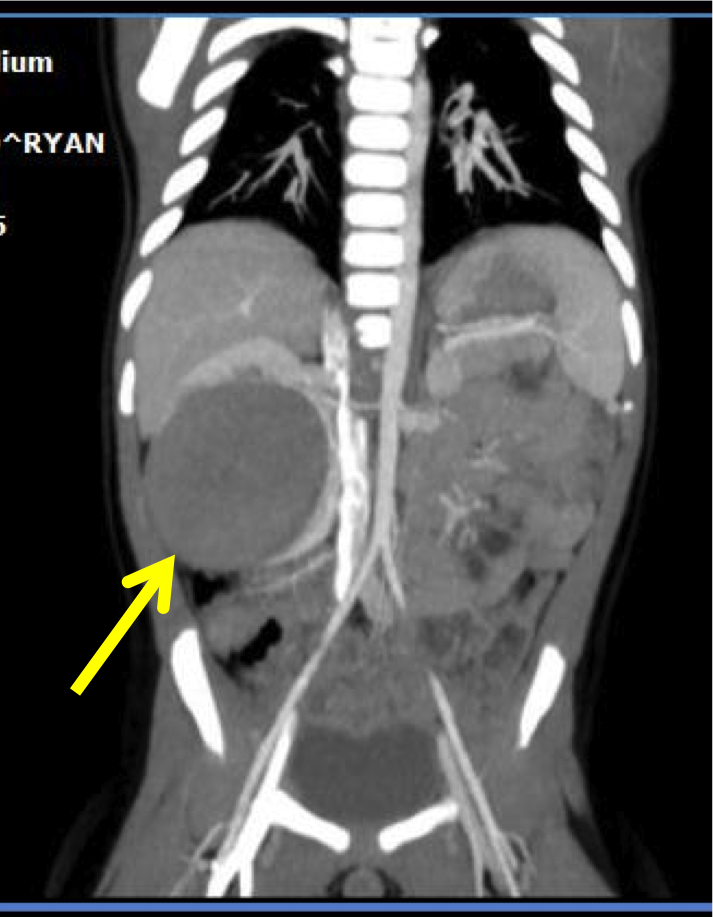

Al bilancio di salute del 1� anno di vita di Ryan, un bel bambino asintomatico e in ottime condizioni generali, il pediatra riscontra una massa addominale in ipocondrio destro, per cui lo invia in PS per ulteriori accertamenti. All'arrivo in PS il bambino � spaventato dalla presenza di tanti visi nuovi, non si lascia visitare, piange e scalcia, mentre dal curante si lasciava valutare tranquillo. Gli esami ematici sono nella norma, salvo per lieve leucocitosi linfocitaria e minimo aumento dell'LDH. L'ecografia addominale conferma il sospetto del curante, con evidenza in ipocondrio destro di una formazione solida rotondeggiante di 7 cm isoecogena al parenchima renale, dislocante il rene destro. Nel sospetto di neoplasia, viene eseguita TAC total body che conferma la presenza della massa senza altri reperti significativi (Figure).

Considerato l'imaging suggestivo di nefroblastoma localizzato e l'assenza di fattori di rischio chirurgici, Ryan viene subito sottoposto a intervento di nefroureterectomia destra con risparmio del surrene omolaterale e asportazione radicale della massa, con conferma istologica di tumore di Wilms, stadio I. Per il riscontro di microinfiltrazione capsulare il piccolo viene avviato a chemioterapia neoadiuvante di 6 settimane secondo il protocollo AIEOP (vincristina e actinomicina D), ben tollerata, con remissione completa di malattia.